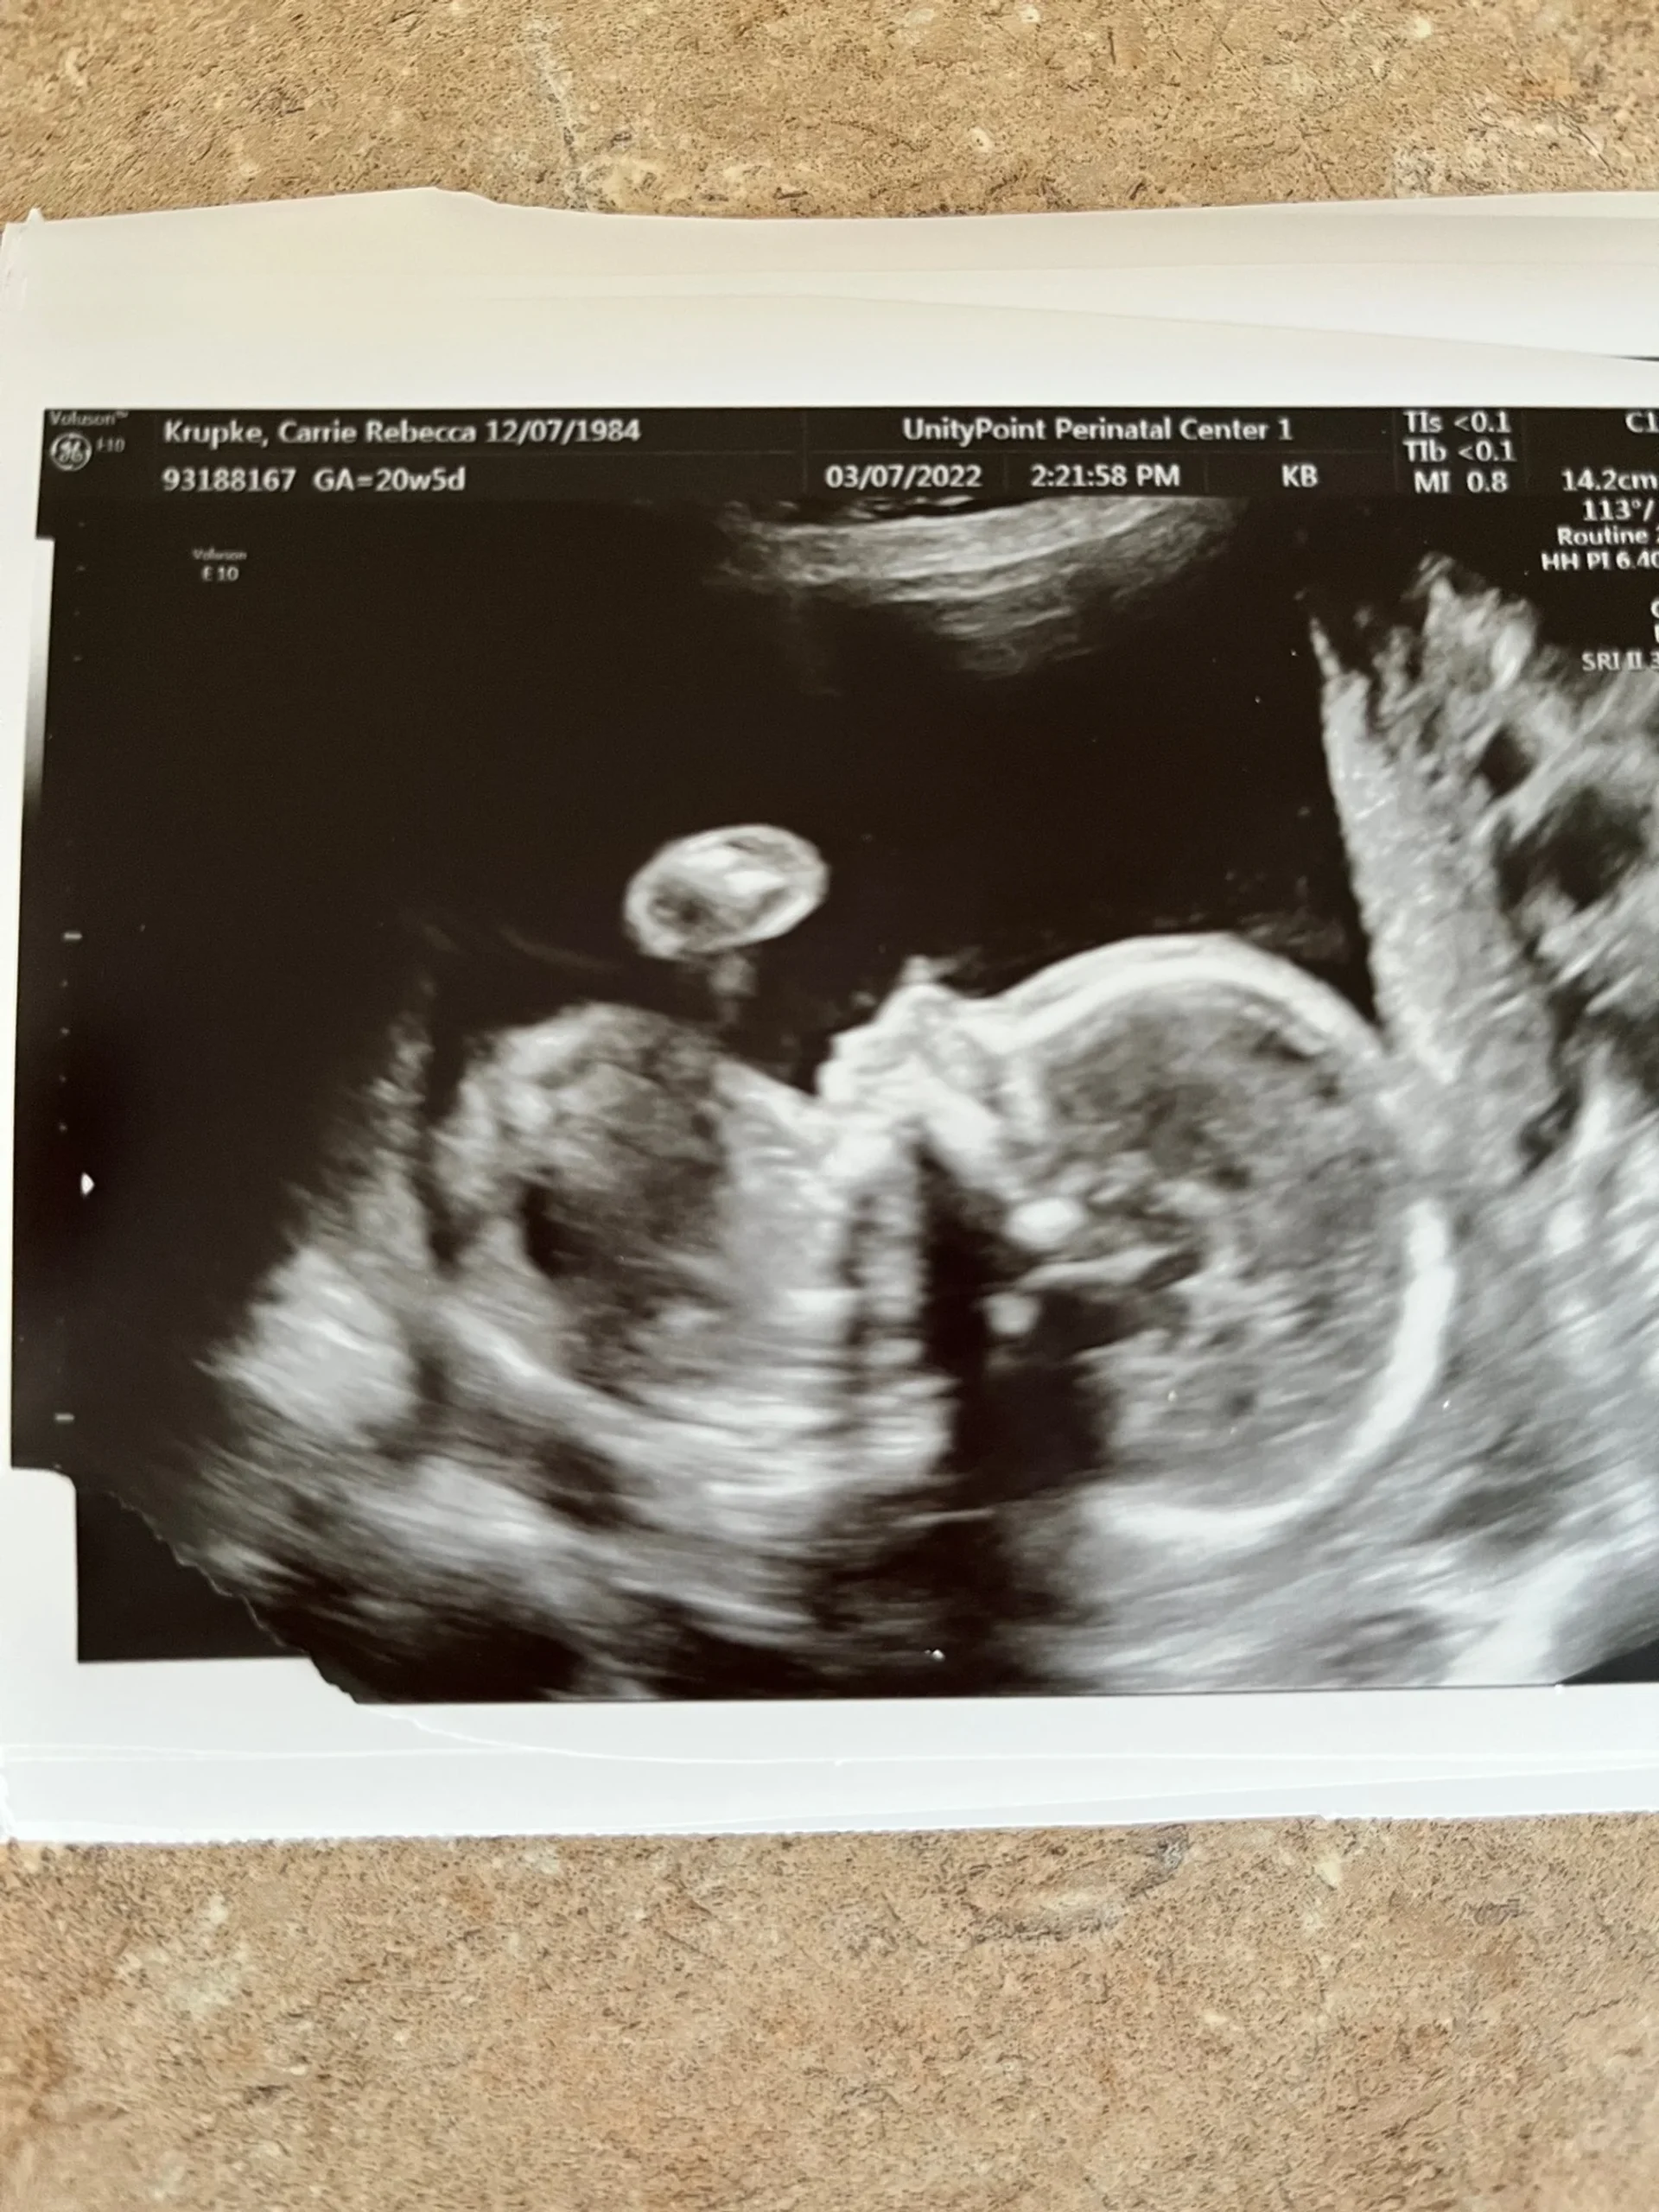

Thankfully, all imaging of Baby Six at her 20 week ultrasound checks out to be developing as it should-spine, brain, heart, kidneys, everything is right on track. After the last 12 months our family has had, I keep waiting for catastrophe to strike but as my Mom said, “She is the best thing that has come out of 2021. Take it and RUN!” 🙂